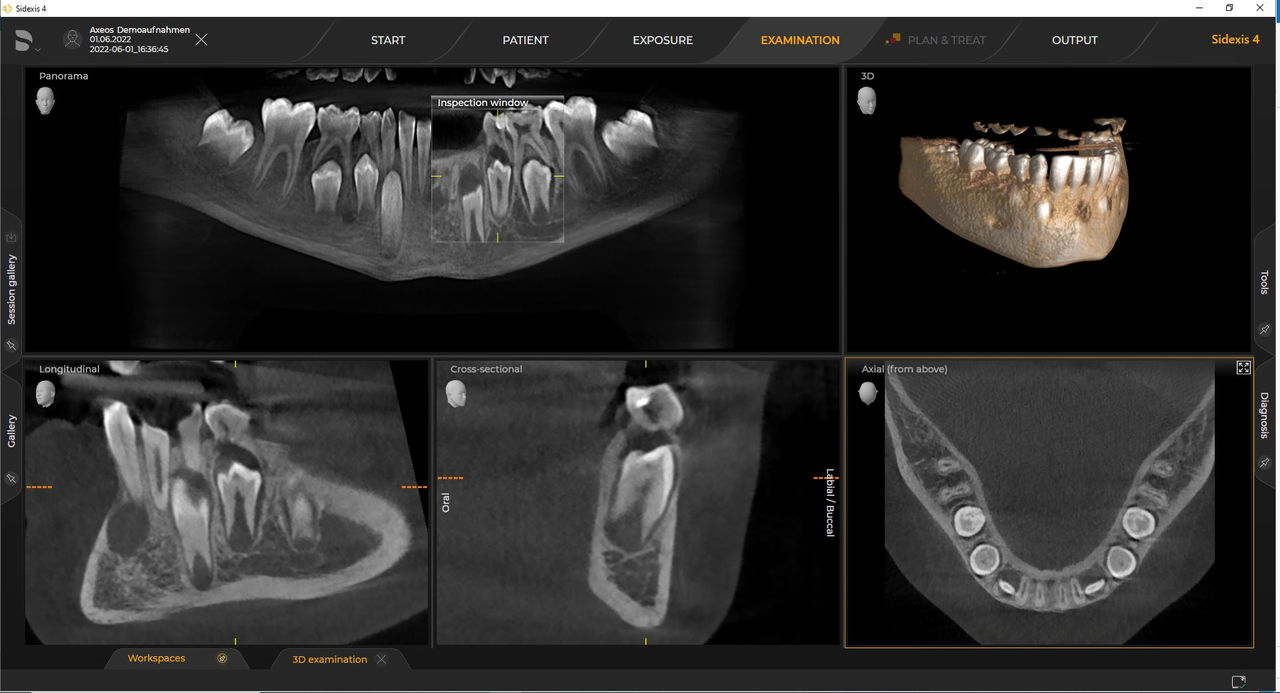

Das 2D-/3D-System mit großem Volumen und hoher Bildqualität für Praxen mit breitem Behandlungsspektrum. Gemeinsam mit Zahnärzten und Behandlern entwickelt, bietet Axeos von allen Dentsply Sirona Extraoral-Röntgengeräten das breiteste Behandlungsspektrum. Neben einer exzellenten Bildqualität und maßgeschneiderten 3D-Volumengrößen zeichnet sich das Röntgengerät durch einen hohen Patientenkomfort aus. Axeos bietet nicht nur Qualität bei Leistung und Komfort, sondern überzeugt auch durch sein preisgekröntes Design mit einem integrierten Aufbiss-Ordnungssystem und Ambient Light

Zahlreiche Volumengrößen sorgen für Flexibilität im Praxisalltag. Untersuchung eines bestimmten Bereichs oder Beurteilung der gesamten Bezahnung einschließlich der Kiefergelenke.

Mit dem Intelligent Low Dose-Modus erhalten Sie 3D-Bilder im Dosisbereich einer 2D-Röntgenaufnahme. Im HD-Modus werden während eines einzelnen Umlaufs bis zu 1.400 Einzelbilder aufgenommen und zu einem 3D-Volumen mit bis zu 80 μm zusammengeführt. Der Vorteil für Sie: rauschärmere Aufnahmen in hoher Auflösung.